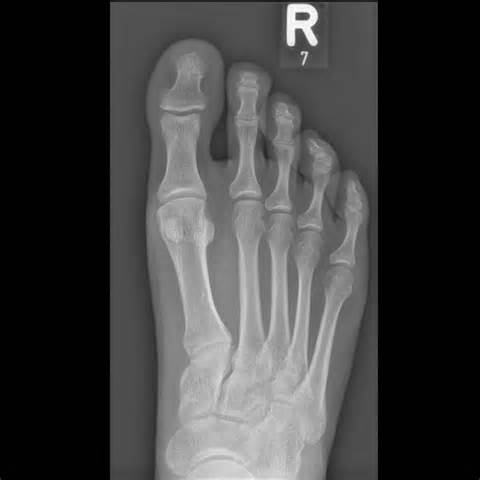

After about 20 minutes (and a few games of Candy Crush Saga) I got called into the back room to recite my entire health history and to get a few X-rays of my starboard side tootsie. Say cheese!

His initial words: “I want to check first for signs of a stress fracture.”

“Nope, it looks good.”

So after Dr. Wang did some bending and poking (of my feet, you perverts) the prognosis was actually quite good.